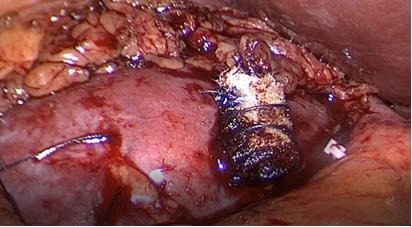

Nefrectomía radical en casos complejos

En relación al tamaño del tumor renal para la vía de abordaje, se ha demostrado que masas renales de > de 10 cm de diámetro, se pueden operar por vía laparoscópica. Determinamos que si los tumores son clínicamente localizados, el tamaño no fue un impedimento para la cirugía. Otros grupos presentaron experiencias similares y concluyeron que no hay diferencias en los resultados, tanto quirúrgicos como oncológicos (21,22) (Figura 22).